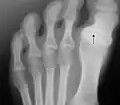

A right foot with hallux varus

Hallux varus, also commonly referred to as sandal gap, is a clinical condition characterized by medial deviation of the great toe at the metatarsophalangeal joint.[2] This condition, when acquired by adults, is usually caused by sports injury, surgical overcorrection of hallux valgus, or underlying causes such as arthritides.[2]